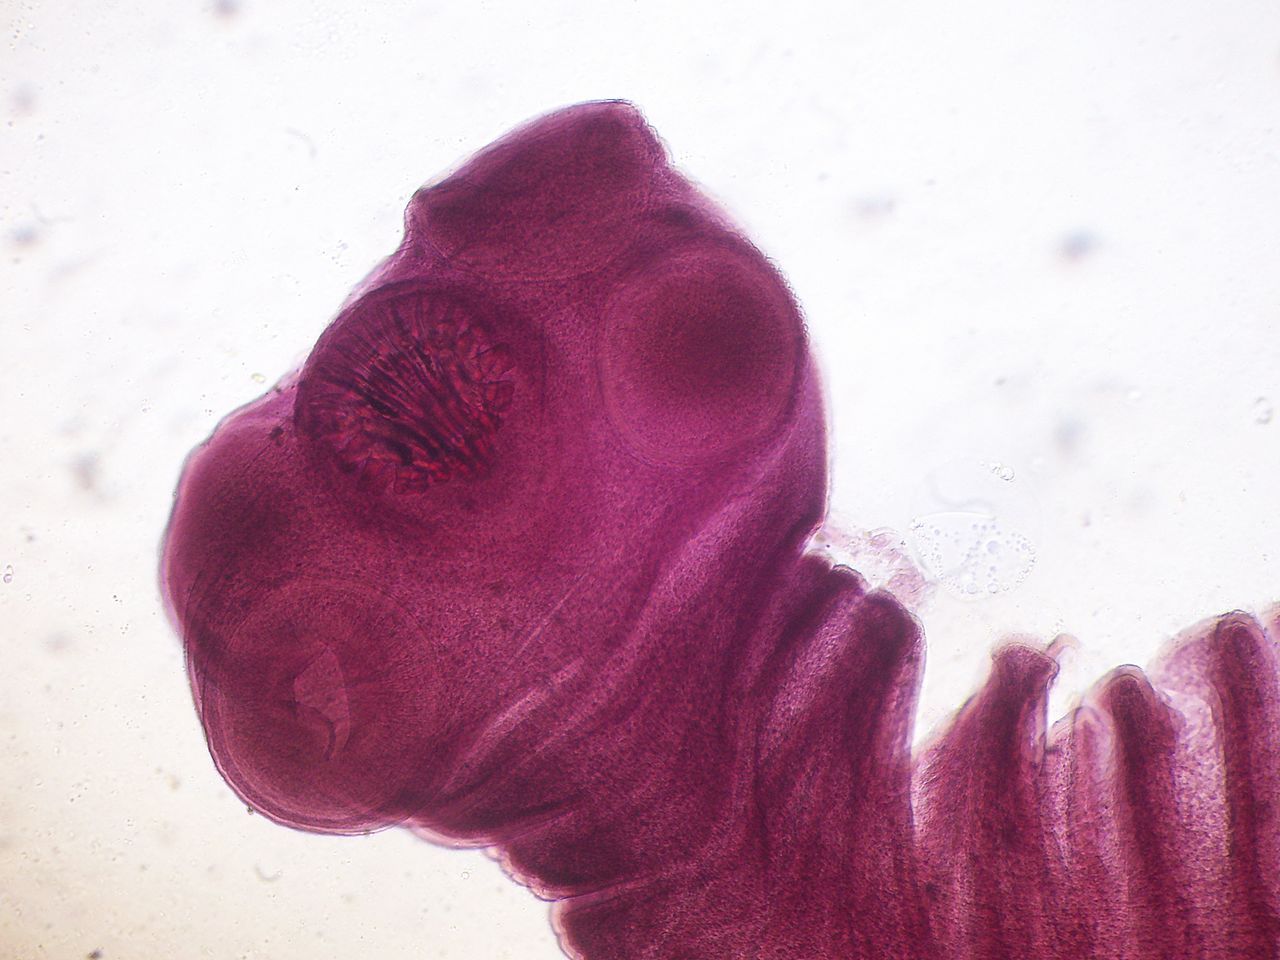

寄生虫检验 #猪带绦虫

猪带绦虫的成虫寄生在人的小肠中,中间寄主为猪故得名.

猪肉绦虫,学名为链状带绦虫,成虫寄生于人体肠道,可以引起猪带绦虫病